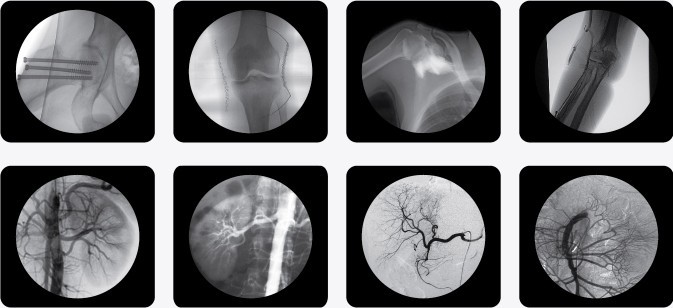

科技的日新月異使得我國醫(yī)療器械有了翻天覆地的變化,尤其是放射科設(shè)備。移動式C型臂X光機(jī)被稱為為可移動的C形臂的X光機(jī),又叫C臂X光機(jī)、C臂機(jī)、百萬像素C型臂、C臂、小C型臂、骨科C臂等。主要用途有:1、骨科:整骨、復(fù)位、打釘;2、外科:取體內(nèi)異物、心導(dǎo)管、植入起搏器、部分介入治療、部分造影術(shù)及局部攝影等工作;3、其他:配合臭氧機(jī)治療疼痛,小針刀治療,婦科輸卵管導(dǎo)引手術(shù)等。已經(jīng)被多個科室引入使用。

移動式C型臂X光機(jī)由機(jī)柜,監(jiān)視器,逆變器,機(jī)頭,影像增強(qiáng)器,數(shù)據(jù)處理系統(tǒng),控制臺以及C組成。小C臂操作起來非常方便,擺好C的位置后(在擺C的時候 讓影像增強(qiáng)器盡量靠近被照射部位,以獲得更好的圖像效果)踩下透視腳閘,機(jī)頭中的球管發(fā)出射線,透過被照射部位后的射線被影像增強(qiáng)器捕獲,后轉(zhuǎn)變成一束綠光后被CCD攝像機(jī)攝取后轉(zhuǎn)變成電信號,然后輸入圖像處理系統(tǒng),在圖像處理系統(tǒng)處理后輸出到監(jiān)視器,即完成了透視工作。醫(yī)務(wù)人員可以在監(jiān)視器上面看到被透視部位的密度像。

以下是南京C型臂X光機(jī)PLX7000C的產(chǎn)品參考圖,點(diǎn)擊產(chǎn)品圖下方紅色的產(chǎn)品名稱可以直接進(jìn)入詳情頁面:

(普朗品牌產(chǎn)品--C型臂X光機(jī)PLX7000C